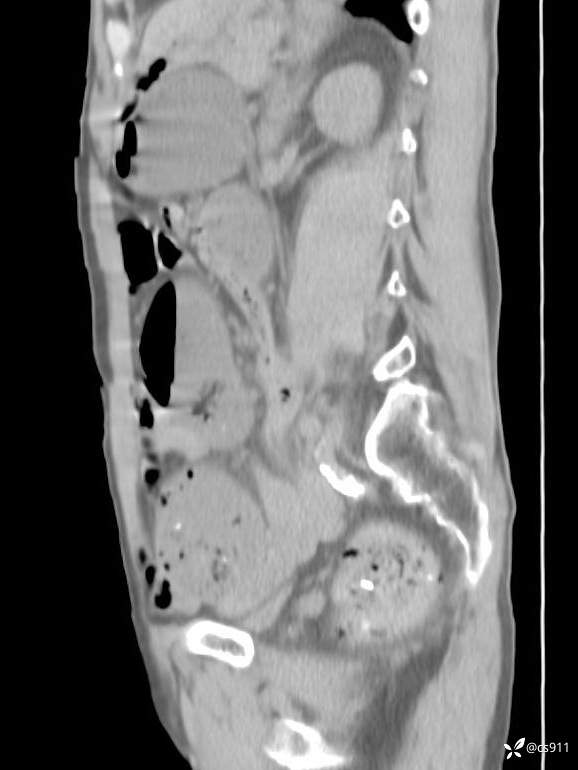

急腹症之急诊CT,原因?答案公布

男,77岁,腹痛、腹胀伴恶心呕吐1天。呕吐胃内容物,非喷射性呕吐,有咖啡色样胃内容物,诉有胃穿孔病史。查体:全腹平,下腹部压痛,全腹无反跳痛,叩诊呈浊音,移动性浊音阴性,肠鸣音减弱,1-2次/分。肛检:直肠未扪及明显肿物,可触及大量粪块。

血淀粉酶(AMY) HH 1859 U/L 35-135